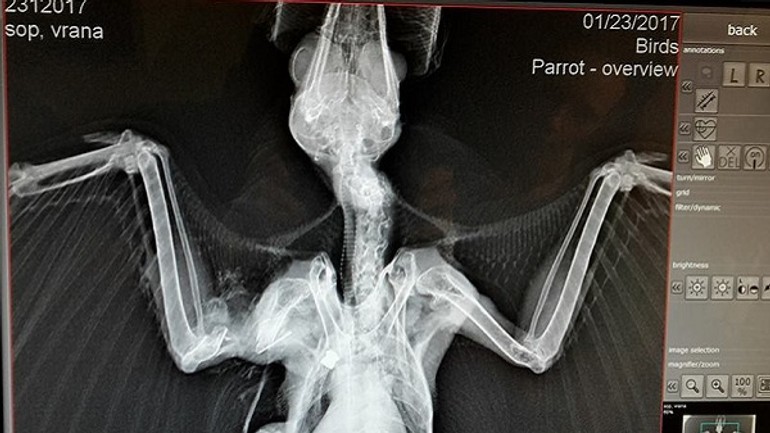

Opakované prípady zástrelu havranov a vrán z Vrakune. Táto vrana bola odchytená v jednej zo záhrad, odkiaľ nevedela vzlietnuť s podozrením na zlomeninu krídla. Röntgen však odhalil skutočnú príčinu,  uvádza na sociálnej sieti Regionálne centrum ochrany prírody Bratislava a Správa CHKO Dunajské luhy. Ochranári zverejnili aj röntgenovú snímku zraneného vtáka a upozorňujú, že všetky druhy vtákov s výnimkou holubov sú zákonom chránené.